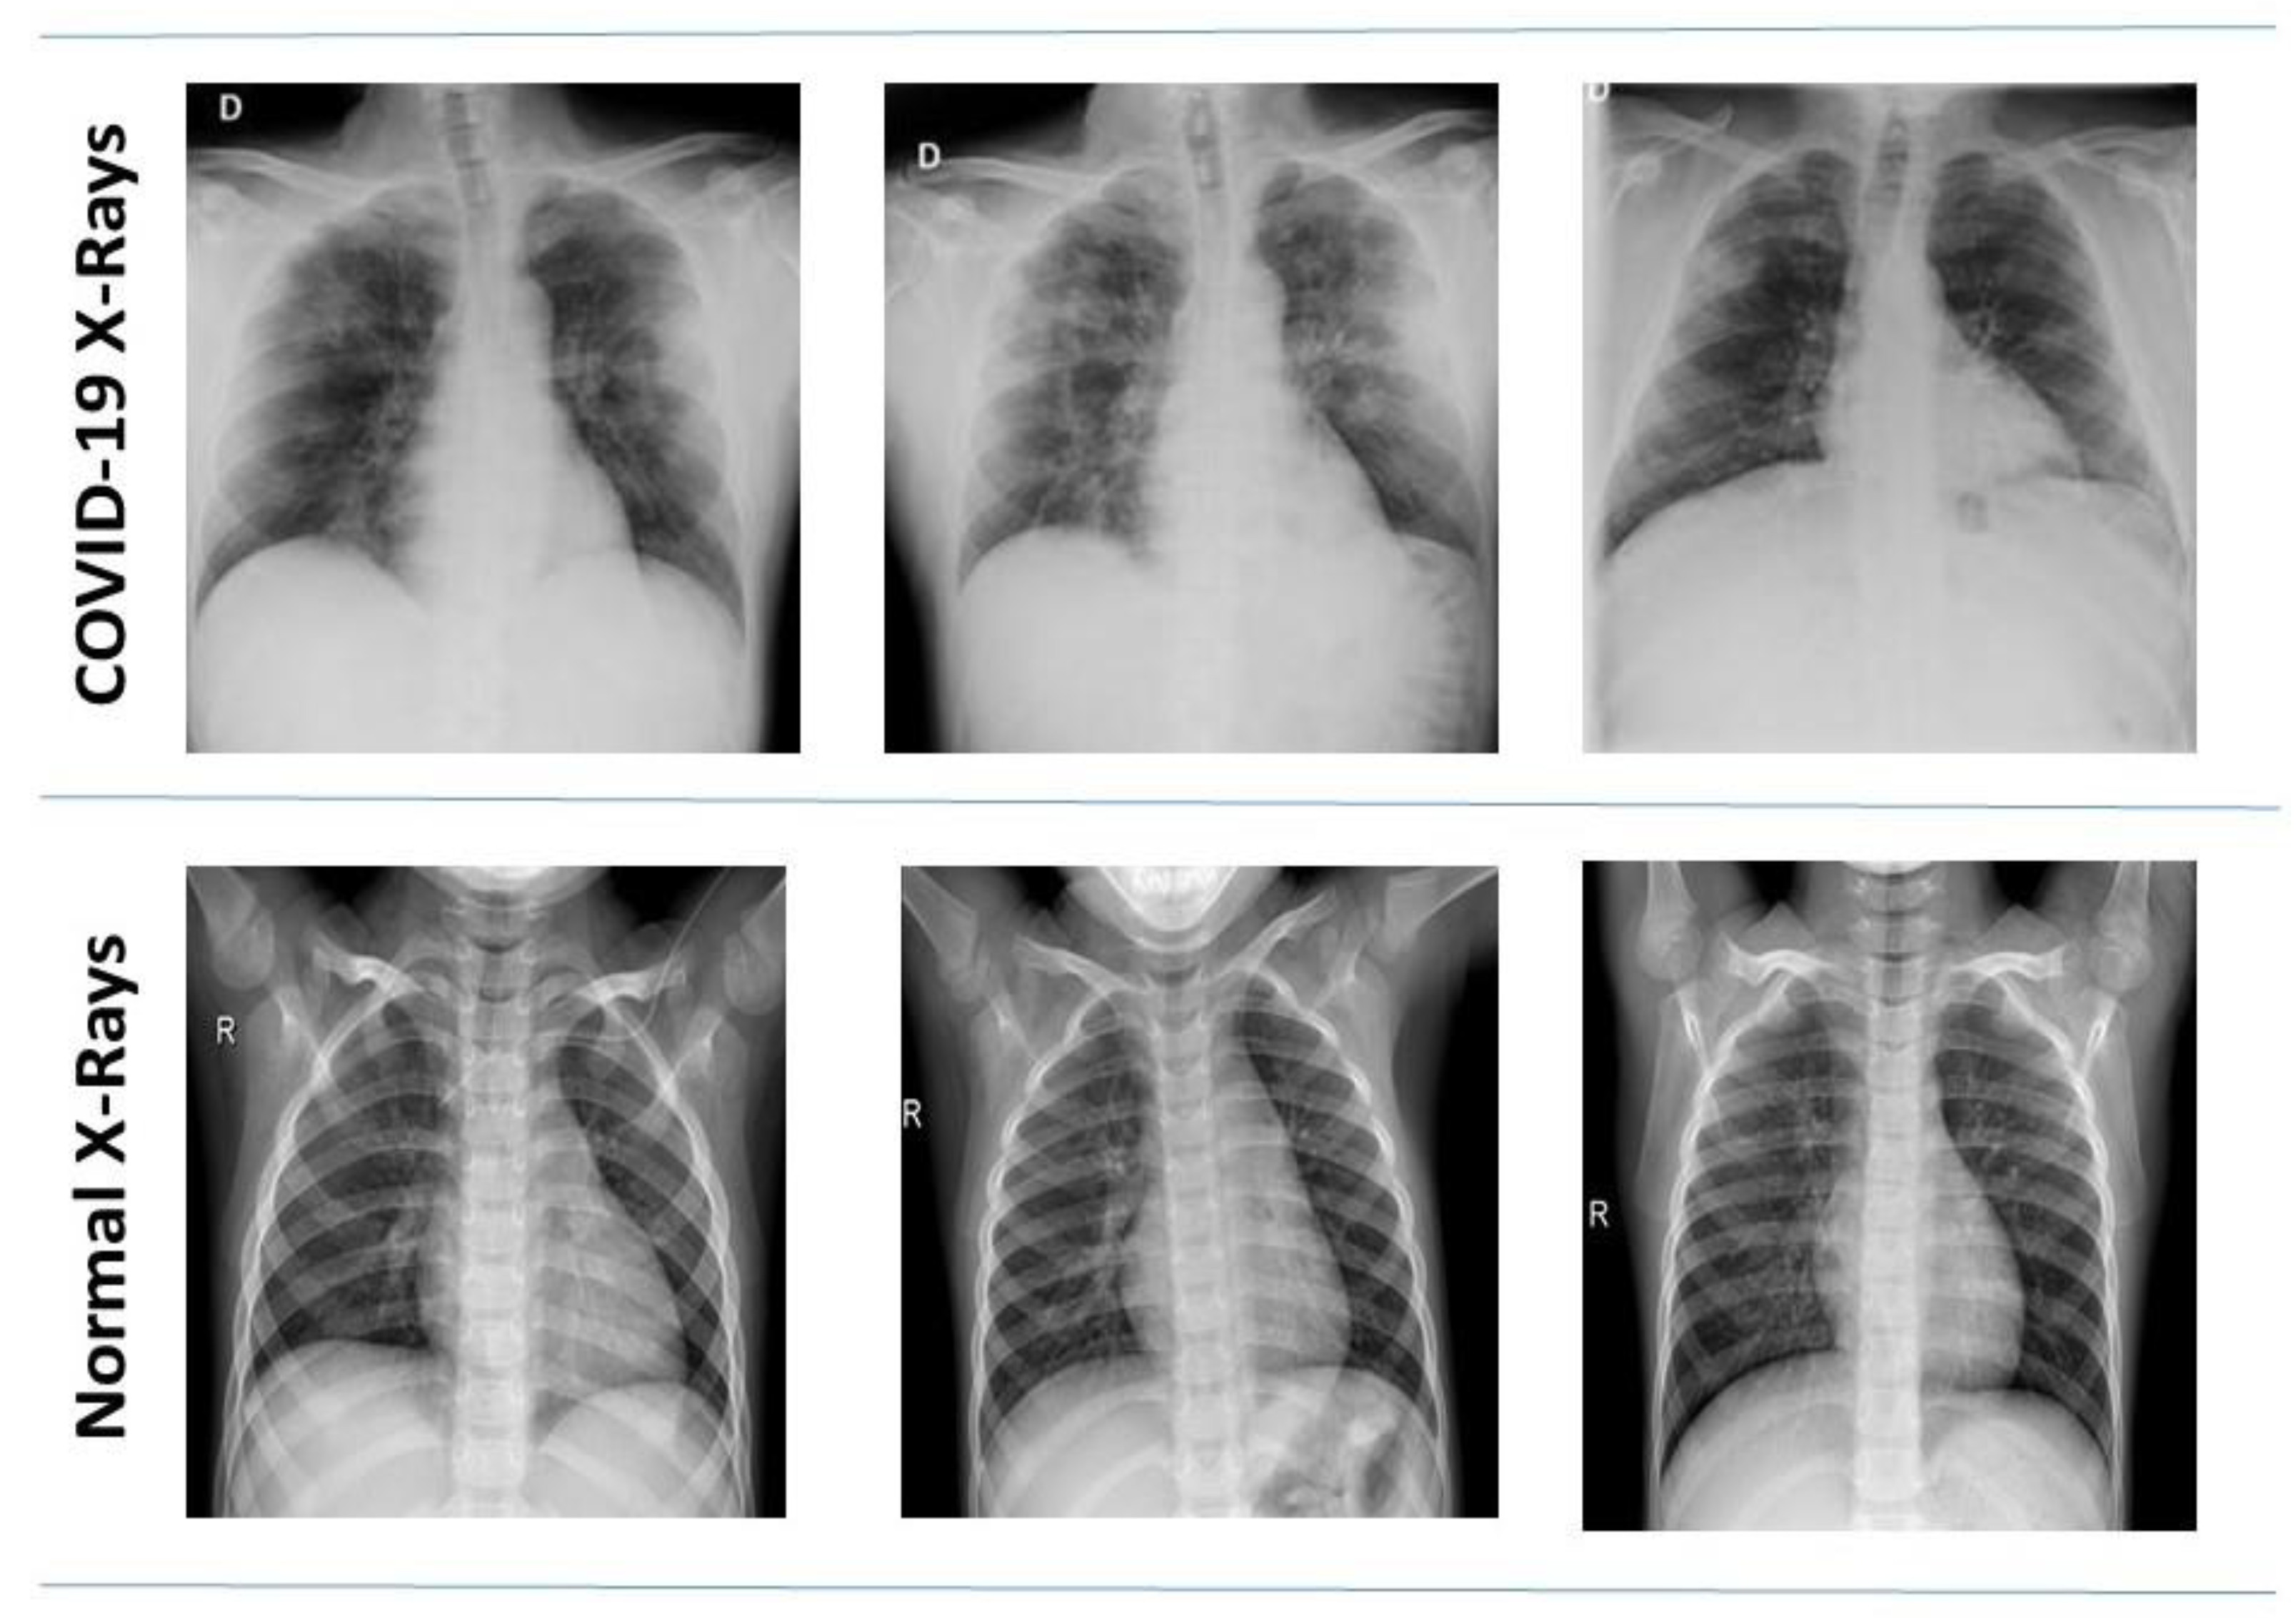

3.1. Dataset

3.1.1. Kaggle COVID-19 Radiography Database

3.1.2. COVID-19 Chest X-ray Dataset by Joseph Paul Cohen

3.1.3. Data Distribution